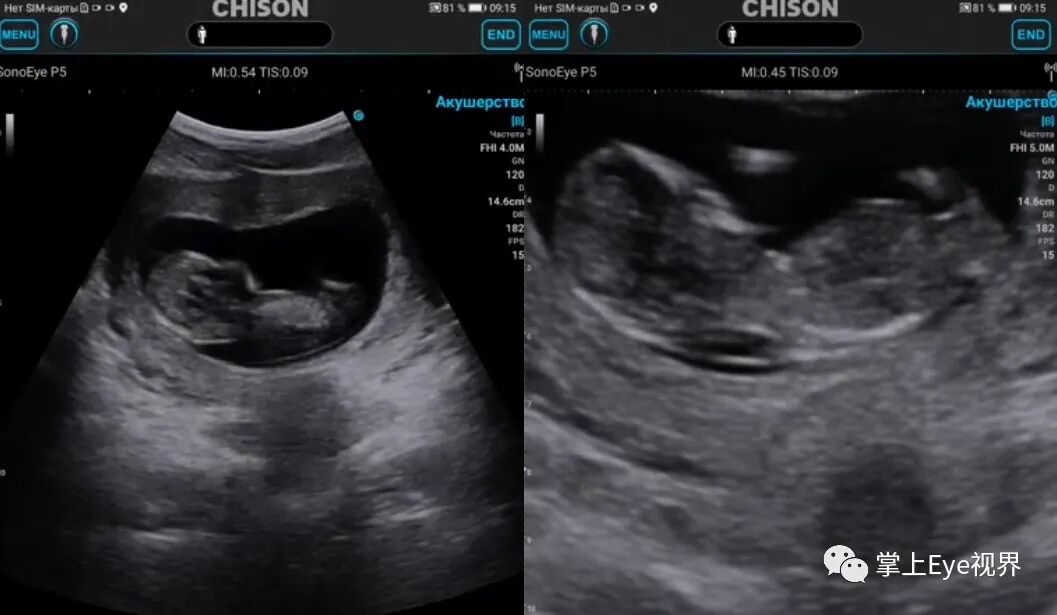

SonoEye V5低频凸阵超声